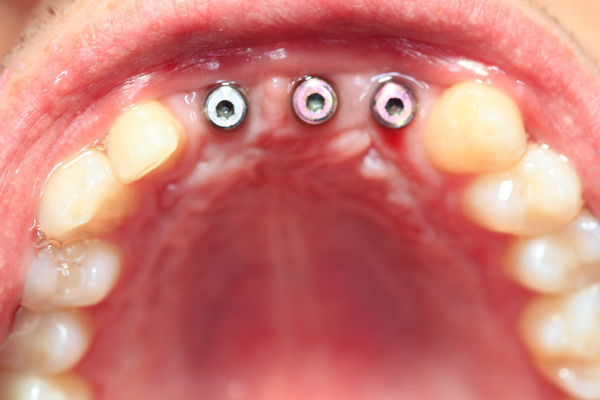

Problem: This young man was hit by a car while riding his bike. He had multiple fractures in his jaw and three front teeth were fractured.

Plan: Our plan… his fractures were fixed. The trauma left a bony defect which was grafted as well as soft tissue VIP grafts. Placed three separate implants with guided surgery. Molded the tissue and placed Zirconium abutments with porcelain crowns.

A great young man with a confident smile.